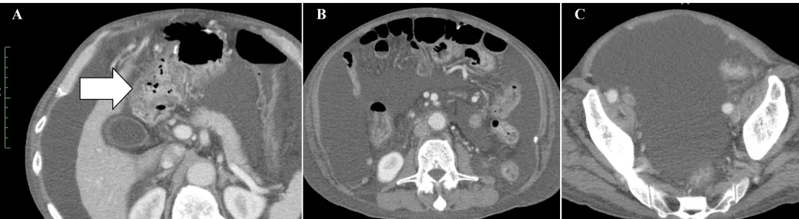

小细胞未分化宫颈癌进展快、易耐药,预后极差。《Cureus》报道了一则突破性案例:一位 50 多岁的患者术后出现肝、淋巴结多处转移,化疗失败后,采用 WT1-DC 疫苗联合放疗: 1、第 67 天(注射第 5 剂疫苗后),CT 显示肝转移灶完全消失; 2、免疫指标(中性粒细胞 / 淋巴细胞比值等)恢复正常,原本因化疗受损的免疫功能显著改善。 案例3:胰腺癌患者中位生存期突破3年,7人成功手术 胰腺导管腺癌被称为 “癌王”,对放化疗天然耐药。《癌症免疫治疗杂志》的一项研究带来了新希望:10 例不可切除的胰腺导管腺癌患者(6 例 III 期局部晚期、3 例 IV 期转移性、1 例术后复发)采用 WT1-DC 疫苗联合化疗后: 1、所有患者肿瘤负荷下降,7人达到部分缓解,3人长期稳定; 2、9例患者中位无进展生存期 2.23 年,中位总生存期更是突破 3.52 年,远超传统治疗的预期。 3、 7 例成功接受了转化手术,其中 6 例实现 R0 切除(肿瘤完全切除,无残留),1 例为 R1 切除(镜下有残留)。 案例4:晚期十二指肠癌 4.3 年无进展,恶性腹水消失 十二指肠癌占胃肠道癌症的 0.3%-0.5%,虽发病率低但侵袭性强,易快速扩散,根治性手术是唯一可能治愈的手段,但晚期患者往往失去手术机会,且针对恶性腹水缺乏有效治疗方案。 《Cureus》曾报道一则案例:一位 72 岁的晚期十二指肠癌患者,腹膜播散伴恶性腹水,化疗失败后接受 WT1/MUC1-DC 疫苗联合细胞疗法: 1、第 8 次治疗后,恶性腹水消失,腹胀、水肿等症状消退; 2、原发病灶和转移淋巴结缩小,截至报道时,肿瘤 52 个月未进展,患者未出现严重副作用,且能正常活动。 锐赛EP-DC(医迪泰)是一种通用型的DC细胞疫苗,可靶向激活免疫系统对22种常见肿瘤抗原的免疫反应。产生强大免疫应答(CD4+/CD8+)识别所有肿瘤抗原,并覆盖广泛HLA类型。 当向患者给药时,医迪泰诱导的免疫应答有可能识别及破坏体内的癌细胞并向免疫系统持续提供支持和记忆,以便其能够持续靶向及预防癌症复发的可能。 2025年初,顶尖期刊Small Science(IF 12.7)发表了太阳成集团官网首席科学家范小勇教授与复旦大学附属上海市公共卫生临床中心研究组、南方科技大学附属深圳市第三人民医院/国家感染性疾病临床医学研究中心研究组的合作研究,题为“Dendritic Cell Vaccine Harboring Inactivated Mycobacteria Induces Immune Protection Against Tuberculosis in Murine Models and is Well Tolerated in Humans”。 本研究在上海市重大传染病和生物安全研究院官网的报道 该项临床研究使用了锐赛自主知识产权的新一代EP-DC疫苗技术。此前,这一创新技术已在多项抗肿瘤、抗HPV病毒治疗的临床研究中被证明有效。本次研究是EP-DC技术在结核病临床研究的重磅亮相。 太阳成集团官网负责制备DC 范小勇教授团队的突破性研究,首次证实DC细胞应用有望成为预防和治疗结核病的新策略。同时也揭示了新一代EP-DC疫苗技术可以在感染疾病的全病程治疗中发挥重大作用。 随着论文的发表,说明锐赛新一代EP-DC疫苗技术的应用场景已从肿瘤治疗的最后防线,扩展至疾病预防、病原微生物清除、病理进展逆转、疾病辅助治疗和术后防复发的全流程。